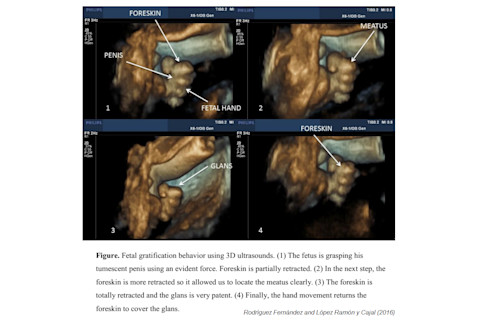

The alleged case of antenatal autoeroticism was reported by Spanish gynecologists Vanesa Rodríguez Fernández and Carlos López Ramón y Cajal in September last year. Their paper was called In utero gratification behaviour in male fetus. Here's the ultrasonic evidence of the act:

Rodríguez Fernández and López Ramón y Cajal wrote that "This is a very clear sexual behavior 'in utero' in the 32nd week of gestation", speculating that the fetus may have been comforting himself by the behaviour. However, not everyone was convinced by these claims. In March 2017, Prenatal Diagnosis published a rather scathing 'Comment' on Rodríguez Fernández and López Ramón y Cajal's paper. The author of the critique was Israeli ultrasound expert Israel Meizner, and he pulled no punches: